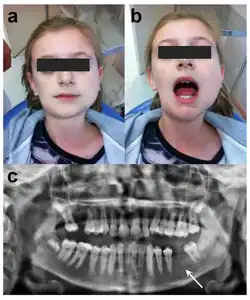

Diagnosis of oral tori are usually done during a dental examination by a dentist or a specialist in dentistry. The bony growth may be recognized during dental procedures, cleanings, or just regular check-ups.

During a routine exam, the dentist may be able to diagnosis this condition through a visual examination by inspecting the mouth for any irregularities such as bony growths. The dentist during this visual exam will focus on the palate, lingual side of the lower jaw, and the outer areas of the upper and lower jaws. Once visual examination indicates an oral torus, the dentist will then feel for palpation in the suspect area in order to further examine the size, shape, and firmness of the oral tori. Though imaging is not necessary to diagnose oral tori, the dentist may decide to do imaging to rule out cysts or tumors (which may cause similar symptoms or have similar factors) by taking an x-ray (for a 2D view) or CT scan (for a 3D view) of the mouth to get a better view of the exact size and location of the growth.[13]